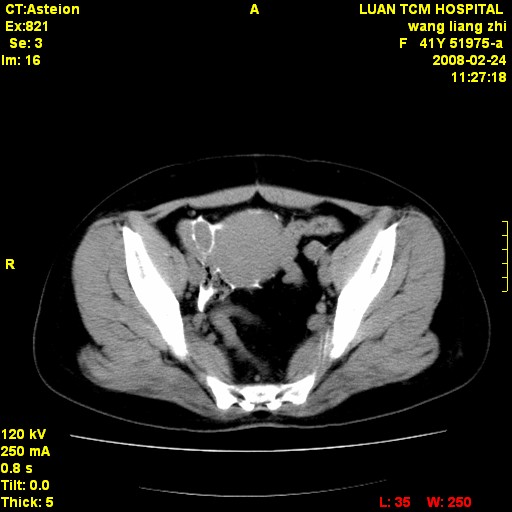

以下是引用dyqct在2009-8-23 16:17:00的发言:[br]考虑:1、造影剂进入腹腔、结肠旁沟、肝周;[br] 2、子宫明显增大(腺肌增生症?);[br] 3、膀胱显影是由于造影剂吸收后经肾分泌进入膀胱的;[br] 4、建议mri检查子宫。

以下是引用zjzjr在2009-8-23 17:28:00的发言:[br]考虑:1、造影剂进入腹腔、结肠旁沟、肝周;[br] 2、子宫明显增大(腺肌增生症?);[br] 3、膀胱显影是由于造影剂吸收后经肾分泌进入膀胱的;[br] 4、建议mri检查子宫。